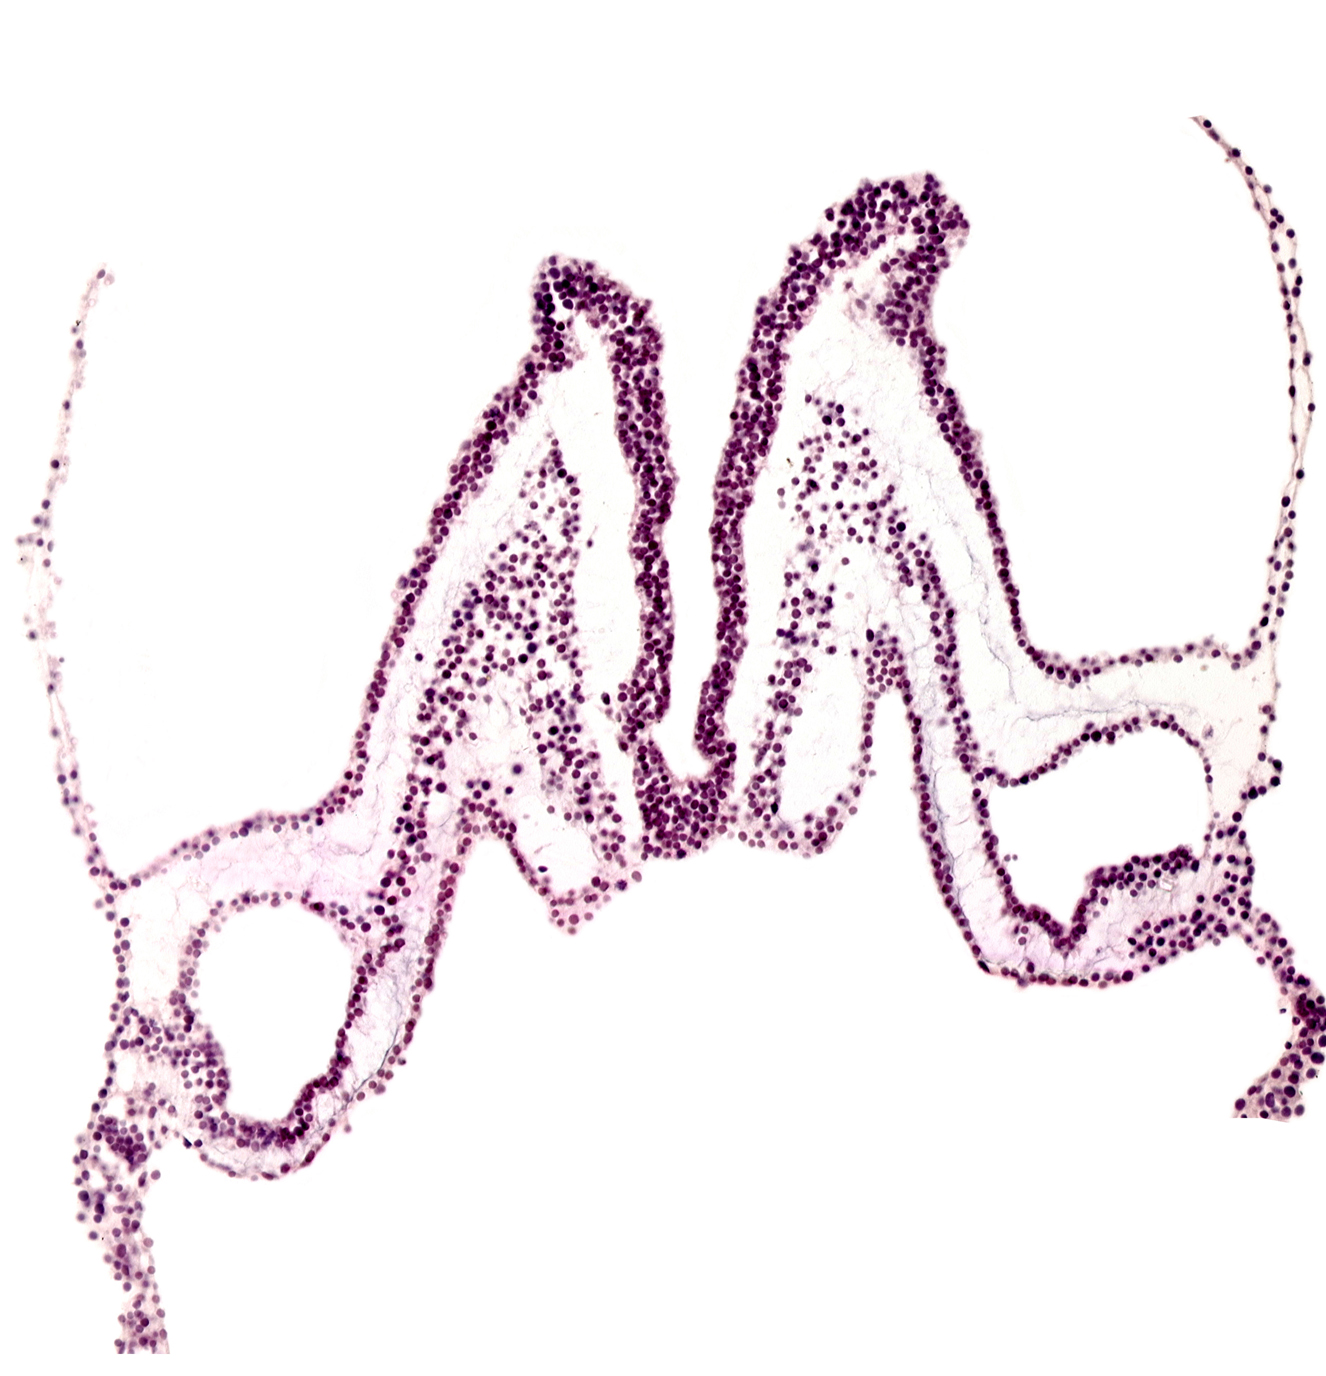

endoderm, extra-embryonic mesoderm, head mesenchyme, neural ectoderm, primordial left dorsal aorta, surface ectoderm

Carnegie Embryo #3709   |   Location: 01-05-02

Keywords: endoderm, extra-embryonic mesoderm, head mesenchyme, neural ectoderm, primordial left dorsal aorta, surface ectoderm

Source: The Virtual Human Embryo.